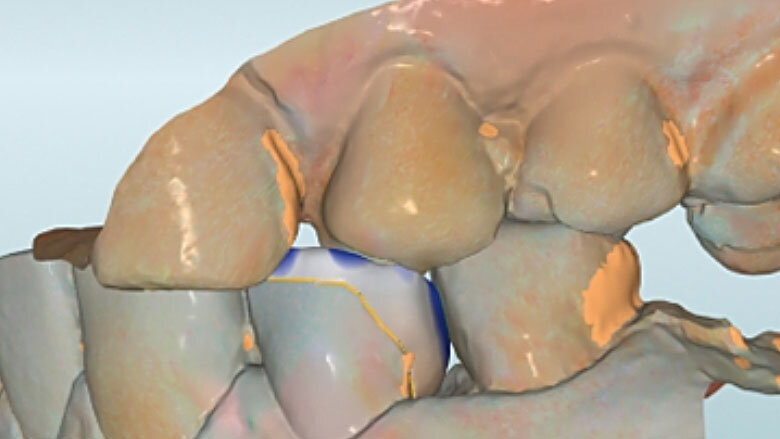

Fig. 5. Tras el escaneo intraoral se estableció el límite de la preparación.

Fig. 6. Mediante un escaneo vestibular se trasladó la intercuspidación habitual.

Fig. 7. Durante el diseño de la restauración se respetaron los grosores de capa mínimos.

Fig. 8. Vista oclusal de la endocorona virtual en el software CAD.

Fig. 9. Vista lingual del diseño.

Antes de la preparación se determinó el color dental 2M2 mediante la VITA Toothguide 3D-MASTER (VITA Zahnfabrik) y se seleccionó la pieza en bruto correspondiente. Se colocó adhesivamente una espiga de fibra de vidrio para incrementar la retención de la posterior reconstrucción de composite. Durante la preparación, únicamente se acortaron las paredes y se incorporó un chamfer en la zona del defecto. Se redondearon sistemáticamente los bordes afilados en la cavidad. Antes del escaneo intraoral fue posible tratar con composite de forma mínimamente invasiva la caries proximal en el diente 34 gracias al buen acceso por mesial.

CAM y acabado